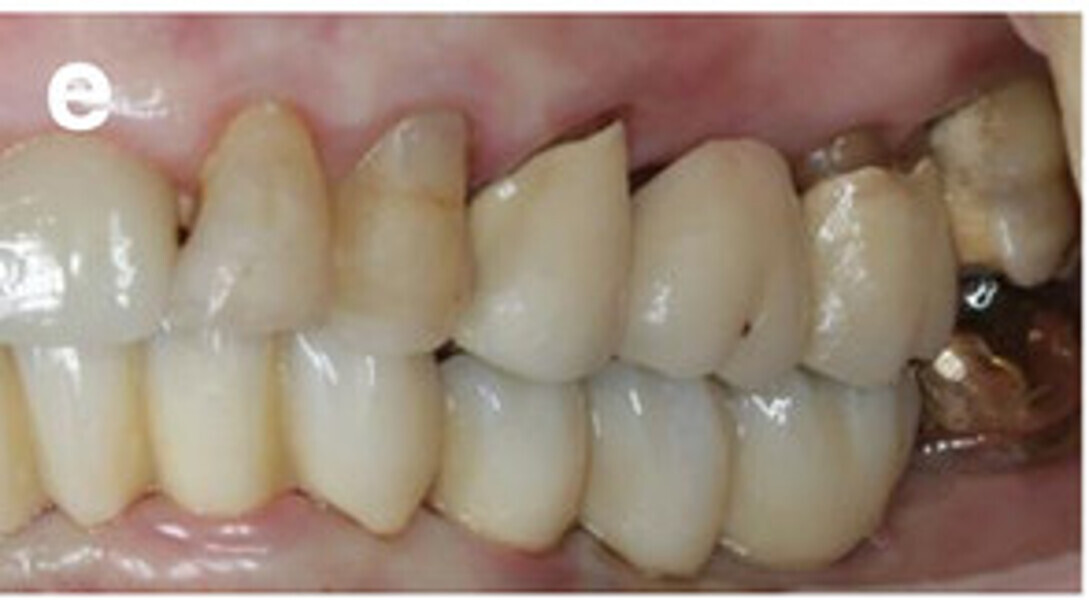

Fig. 14a: Occlusal, frontal and lateral views on the day of delivery, showing healthy peri-implant mucosal conditions (a) and the final CAD/CAM restoration in situ (b–e).

Fig. 14b: Occlusal, frontal and lateral views on the day of delivery, showing healthy peri-implant mucosal conditions (a) and the final CAD/CAM restoration in situ (b–e).

Fig. 14c: Occlusal, frontal and lateral views on the day of delivery, showing healthy peri-implant mucosal conditions (a) and the final CAD/CAM restoration in situ (b–e).

Fig. 14d: Occlusal, frontal and lateral views on the day of delivery, showing healthy peri-implant mucosal conditions (a) and the final CAD/CAM restoration in situ (b–e).

Fig. 14e: Occlusal, frontal and lateral views on the day of delivery, showing healthy peri-implant mucosal conditions (a) and the final CAD/CAM restoration in situ (b–e).